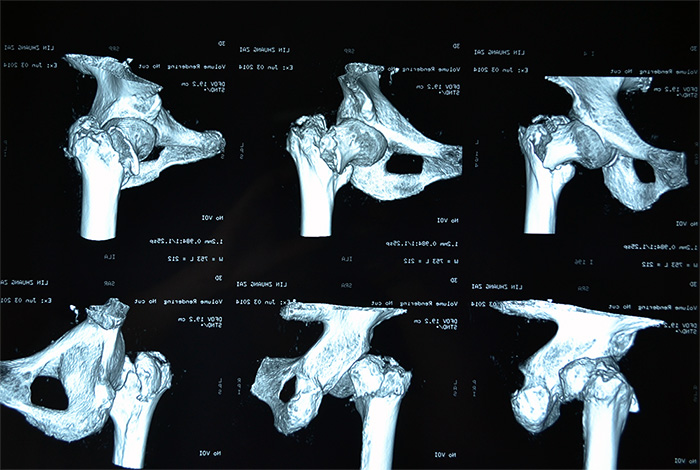

据家属介绍,百岁老人身体还不错,平时生活能自理,还能做家务。5月20日上午,她在洗衣服的时候,由于地面湿滑,摔倒在地,当时左腿就无法站立,送到当地医院拍片,发现左腿髋部骨折严重,且错位明显。考虑患者高龄,骨折严重,手术风险高,技术难度大,当地医院无法完成手术,转入厦门第三医院治疗。

林老太入三院时,左腿的髋部骨折处已翻转90度,还出现短缩移位,左腿比右腿短了5—6公分。由于疼痛,每次大小便,对老人来说都是一次折磨,她也不敢正常摄入食物,导致出现低蛋白,且原先就有高血压的症状,心血管功能比较差,手术风险极高,如果采用传统的骨折开放复位钢板固定术,对于高龄特别是骨质疏松患者,手术失败率很高,同时卧床时间长达三四个月,极易引发并发症。骨科主任刘忠国说。

老人应选择何种治疗方案?第三医院骨科、心内科、麻醉科等多科专家组成的专家组认真仔细分析病情,决定采用髋关节微创植入内固定术。6月4日,老人接受手术,在手术牵引床上,通过C臂X光机透视,不切开骨折端闭合牵引复位,在老人骨折处复位到最佳状态时,刘忠国在骨折处开出5公分的口进行螺旋刀片动力髋固定,最大程度减少手术损伤,促进骨折端提早愈合。